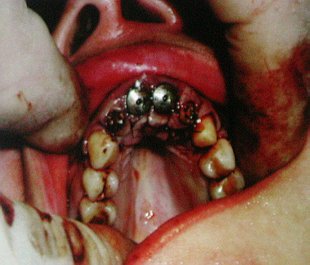

Анализ пятилетнего опыты использования дентальных имплантатов ASTRA TECH стал главной темой выступления доктора Фираса Кики (Клиника эстетической стоматологии "Эстет-Дент" ). В своем докладе он привел массу интересных клинических случаев, в частности, особенности протезирования верхней челюсти. Верхняя челюсть представляет собой совершенно другую картину с точки зрения имплантатного протезирования по сравнению с нижней челюстью. Доступ к кости часто ограничен в связи с сильно резорбированным альвеолярном отростком, что, в сочетании с верхнечелюстными пазухами и носовой полостью, ограничивает наличие кости для поддержки имплантата. Протезирование верхней челюсти имплантатами компании ASTRA TECH AB - Cпециальный репортаж РМС-ЭкспоПериод заживления и период, необходимых для образования плотного костного слоя вокруг имплантатов, удлиняется по сравнению с аналогичными периодами при протезировании нижней челюсти. После завершения оссеинтеграции имплантаты, несущие нагрузку в верхней челюсти, имеют более слабую костную опору по сравнению с имплантатами в нижней челюсти. В то время, как верхняя челюсть 4-5 имплантатами бикортикальной фиксации может держать фиксированный съёмный мостовидный зубной протез 10-12 зубов, для верхней челюсти необходимо большее количество хорошо распределённых имплантатов данного типа протезирования.